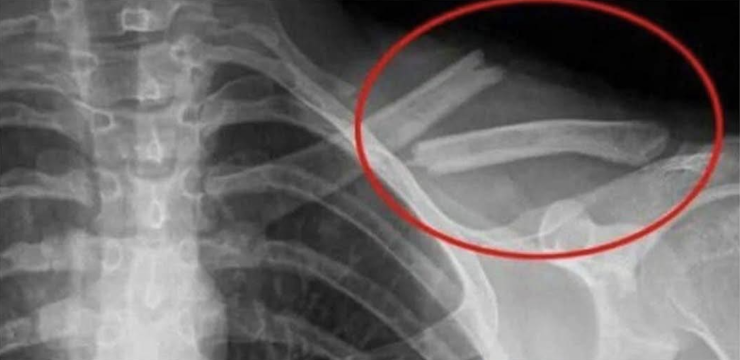

La ricerca è ancora in fase iniziale, ma bere anche solo una bibita dietetica al giorno può aumentare il rischio di frattura all’anca del 14%.

Esiste un chiaro legame tra il consumo di bibite (dietetiche comprese) e la diminuzione della densità ossea. Rinunciare a queste bevande può quindi aiutare a mantenere ossa più forti e sane.